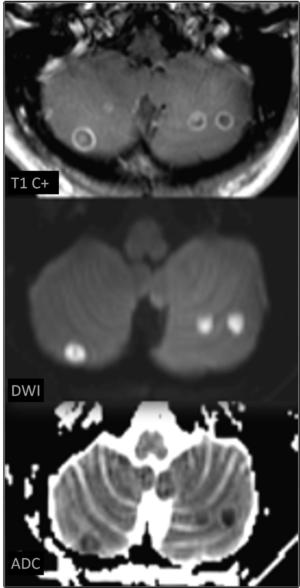

Figure 2. 41-year-old woman with history of heroin IV-SUDs disorder presenting with nausea for 10 days, altered mental status and thrombocytopenia. MRI show multiple ring-enhancing lesions with restricted diffusion in the cerebellum, suggestive of septic emboli.

High-res (TIF) version